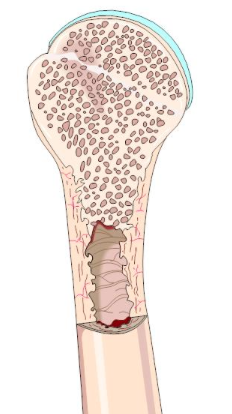

What condition is affecting the bone shown here?

Osteoporosis